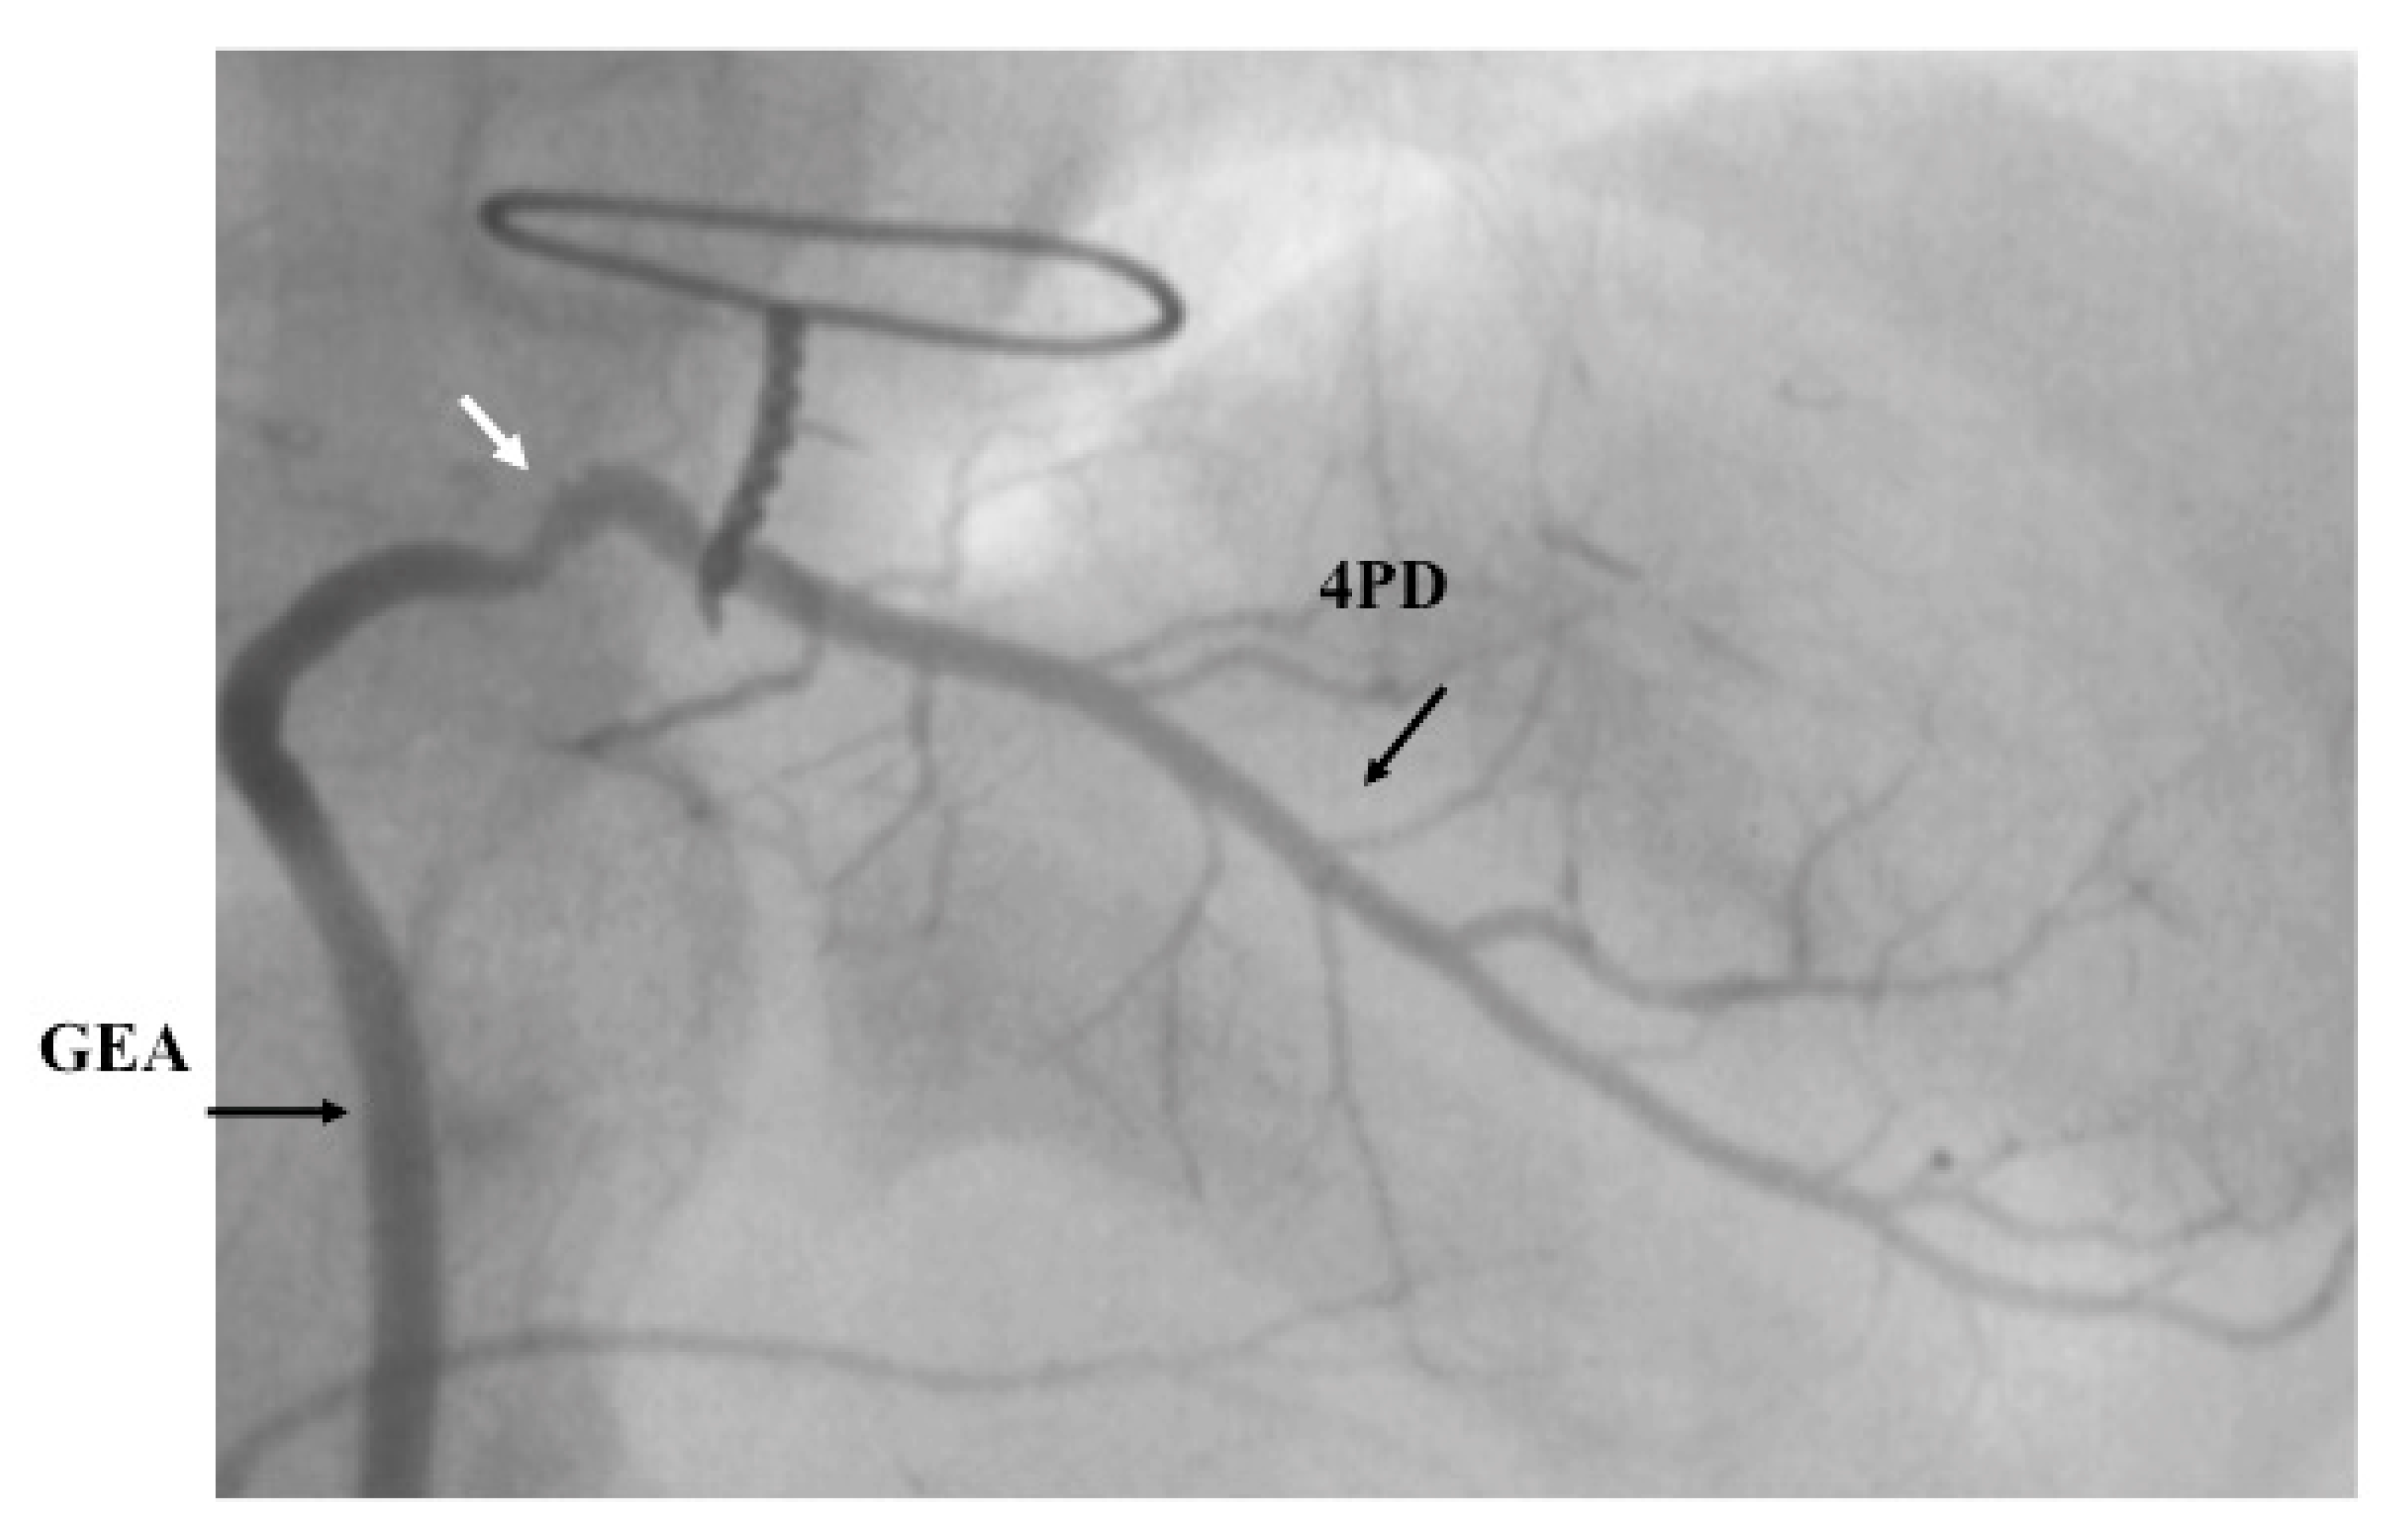

- Takeuchi, Y.; Gomi, A.; Okamura, Y.; Mon, H.; Nagashima, M. Coronary revascularization in a child with Kawasaki disease: Use of right gastroepiploic artery. Ann. Thorac. Surg. 1990, 50, 294–296. [Google Scholar] [CrossRef]